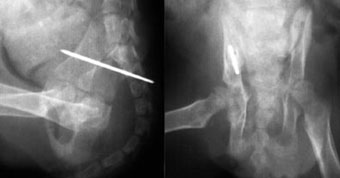

他院からの紹介症例

体重7kg、10か月齢の犬。

腸骨と坐骨の骨折と仙腸関節離断をおこしていました。

腸骨と坐骨はプレート法で整復固定し、仙腸関節離断は創外固定法で整復しました。

写真上段: 手術前

写真下段: 手術後